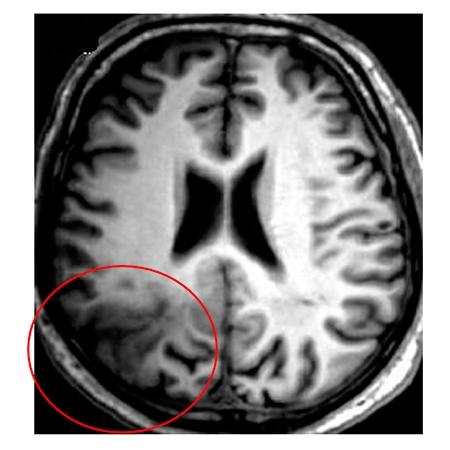

One of the most frequent causes of drug-resistant epilepsy, considered a difficult disease to control, is a brain malformation known as focal cortical dysplasia.

Patients with this problem present with discreet disorganization in the architecture of a specific region of the cortex, which may or may not be associated with the presence of nerve cells that have structural and functional abnormalities.

"Our findings are based on analysis of the brain tissue of 16 patients with type II focal cortical dysplasia, a malformation with cortical disorganization and aberrant nerve cells including dysmorphic neurons that are constantly in a state of excitation and hence favor epileptic seizures," Cendes explained.

In these cases, she added, surgical removal of the malformed area of the brain is the only strategy available to control the symptoms of epilepsy. However, even this is possible only when the malformation is not in a critical brain region such as the motor, somatosensory, auditory, visual, language and other functionally essential networks.